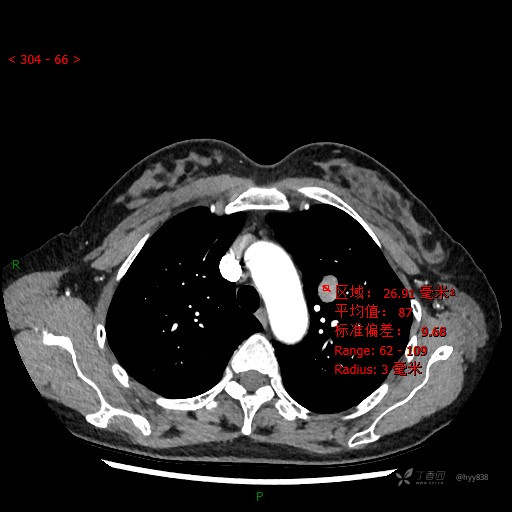

CT值